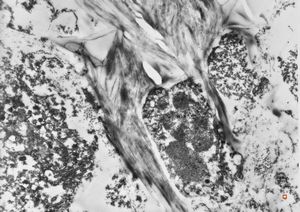

M,67y. | alcoholic hyalin (Mallory body) … autopsy sample